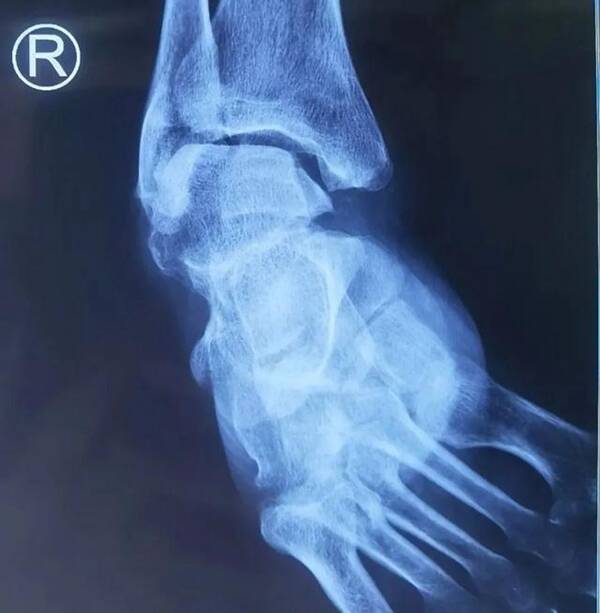

20222月,邯鄲市第一醫(yī)院手足外科應(yīng)用3D打印技術(shù)指導(dǎo)完成一例馬蹄內(nèi)翻高弓足畸形四關(guān)節(jié)截骨矯形融合術(shù)。此項(xiàng)技術(shù)在足踝外科矯形應(yīng)用上取得突破性進(jìn)展,在邯鄲市尚屬首例。該患者60歲男性,后天因素導(dǎo)致馬蹄內(nèi)翻高弓足,長(zhǎng)期右足畸形殘疾,行走極度困難。入住邯鄲市第一醫(yī)院手足外科后,手足外科張曉軍主任、楊金杰醫(yī)生考慮患者嚴(yán)重畸形,踝足各關(guān)節(jié)畸形復(fù)雜,傳統(tǒng)手術(shù)矯正風(fēng)險(xiǎn)較大,考慮應(yīng)用3D打印技術(shù)指導(dǎo)手術(shù),提高手術(shù)精準(zhǔn)性。

術(shù)前通過(guò)ct薄層掃描、計(jì)算機(jī)建模,再用3D打印機(jī)制作模型、術(shù)前測(cè)量規(guī)劃制定手術(shù)方案、術(shù)中精確截骨、指導(dǎo)手術(shù)。避免手術(shù)醫(yī)生主觀誤差,減少術(shù)中透視傷害,使患足術(shù)后達(dá)到良好手術(shù)效果。